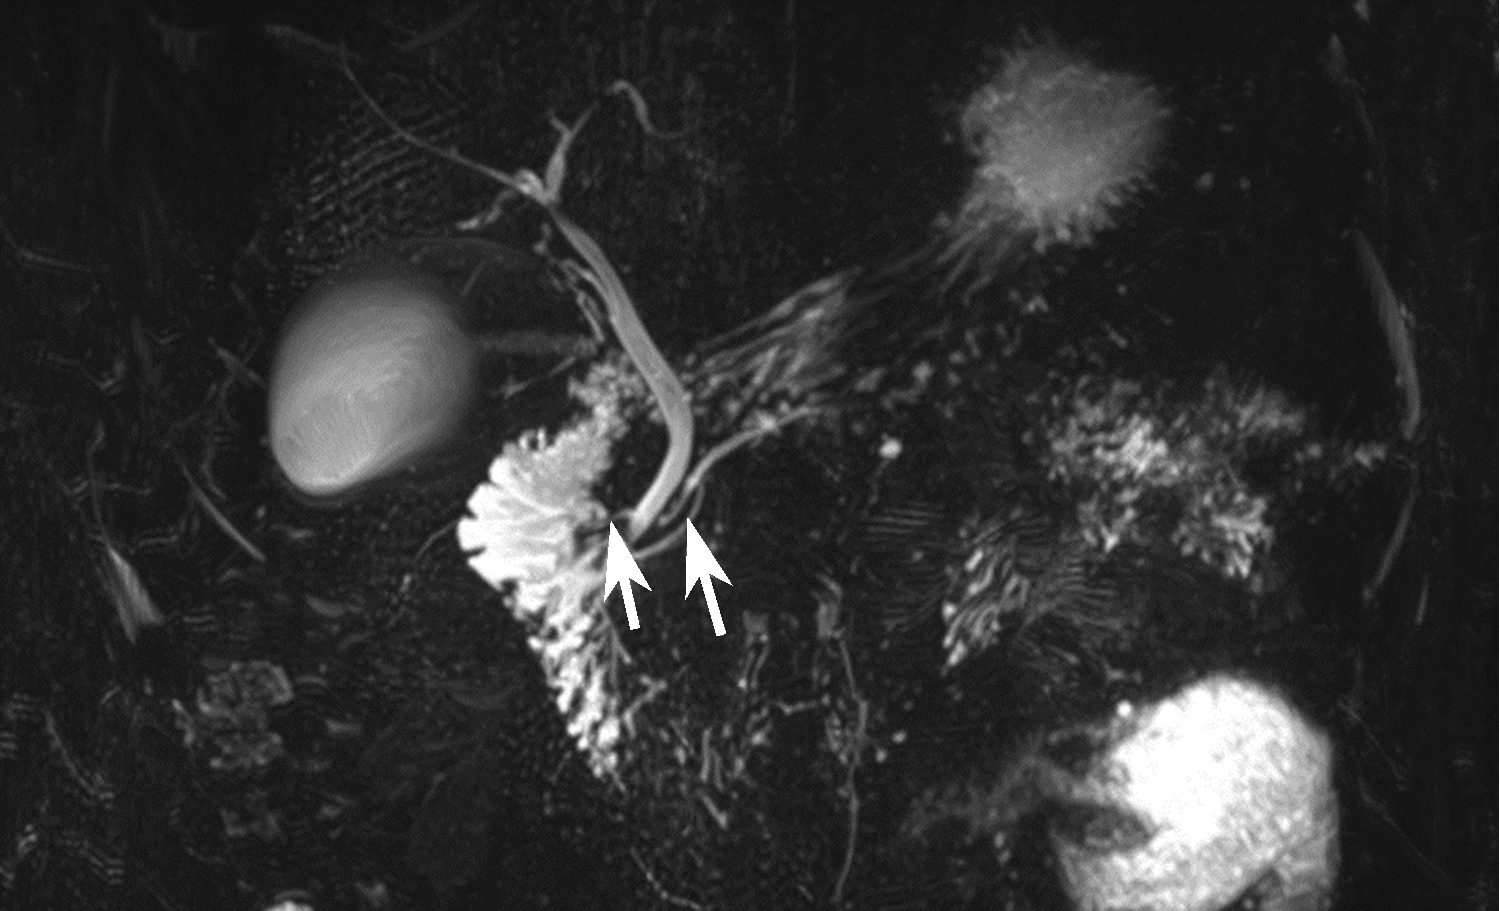

基于超声造影LI-RADS特征的肝细胞癌微血管侵犯列线图模型的构建及验证

2022, 38(11): 2520-2525. DOI: 10.3969/j.issn.1001-5256.2022.11.016

摘要(882) HTML (345) PDF (2938KB)(63)

摘要:

目的  基于肝细胞癌(HCC)患者的超声造影(CEUS)肝脏成像报告和数据系统(LI-RADS)特征建立预测微血管侵犯(MVI)的列线图模型并进行验证。  方法  选取2017年1月—2020年7月在江苏大学附属武进医院确诊的HCC患者共262例,按照1∶ 1比例随机分为建模组和验证组各131例,以术后镜下病理结果确诊MVI,其中建模组MVI 70例和验证组MVI 56例。采用超声造影评估两组的LI-RADS特征。两组间计量资料比较采用独立样本t检验;两组间计数资料比较采用χ2检验。采用单因素和多因素Logistic回归分析筛选建模组MVI的危险因素;绘制受试者工作特征曲线(ROC曲线),计算模型预测MVI的曲线下面积(AUC),评估预测准确度;应用决策曲线分析模型的一致性,比较模型预测MVI的校正曲线与标准曲线的离散度。  结果  建模组与验证组患者的临床资料和CEUS检查结果比较,差异均无统计学意义(P值均>0.05)。单因素分析显示,与MVI阴性患者相比,MVI阳性患者血清AFP水平显升高,肿瘤直径增大,LI-RADS显示LR-5“后出”和LR-M“先出”增多,LI-RADS分级较高,差异均有统计学意义(P值均<0.05)。多因素分析显示,AFP 20~400 ng/mL(OR=2.65,P<0.001)、AFP≥400 ng/mL(OR=3.98,P<0.001)、肿瘤直径≥30 mm(OR=2.12,P<0.001)和CEUS显示LR-M(OR=3.24,P<0.001) 是MVI的独立危险因素。ROC曲线显示,列线图预测建模组和验证组MVI的AUC分别为0.867和0.821。列线图模型的一致性指数C-Index为0.765(95%CI:0.701~0.834)。在建模组和验证组,列线图模型的预测校准曲线与标准曲线均接近。  结论  利用CEUS得出LI-RADS,并结合AFP和肿瘤直径建立的列线图模型有较好的应用价值,有助于指导临床术前筛选MVI高危患者,制订恰当的手术方案。